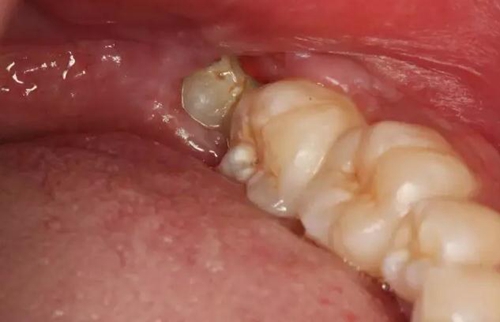

圖4.38頰側牙齦腫脹、探診出血

圖5探診分離牙齦